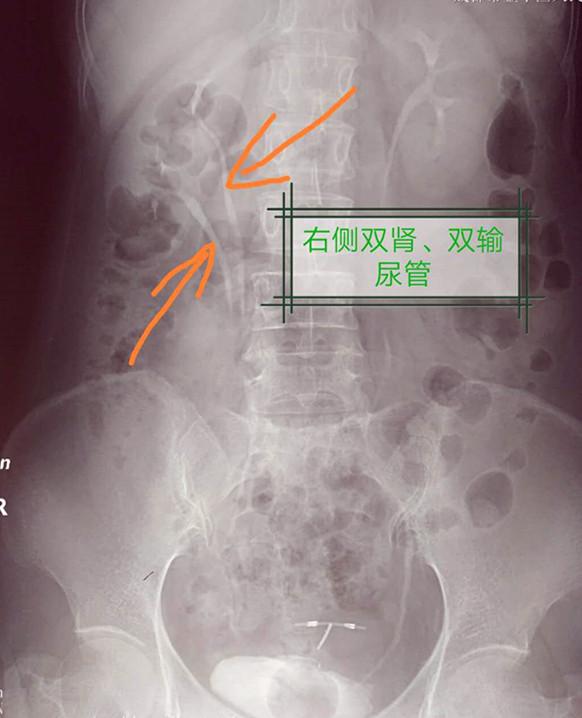

她腰部胀痛,尿频,尿痛2年,原来是"第三个肾脏"在作怪!